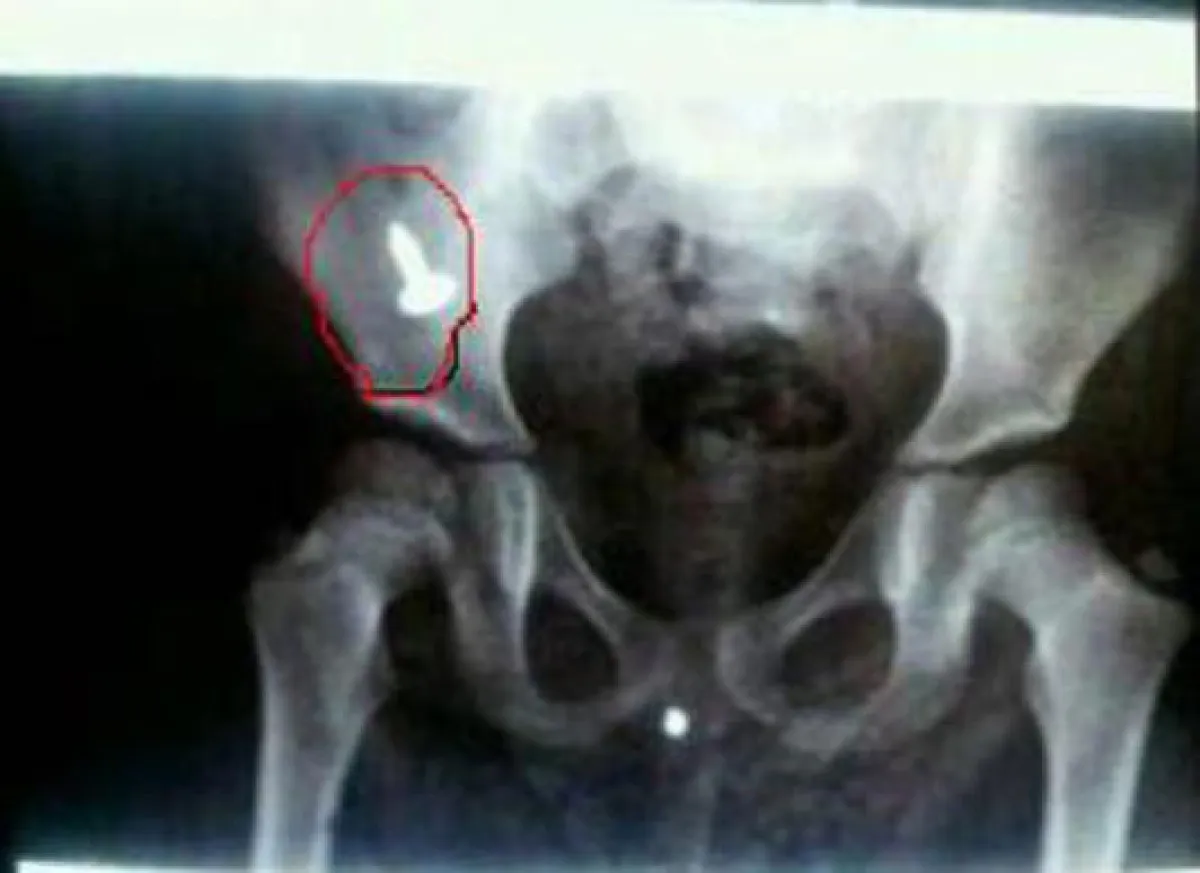

وفي التفاصيل أبلغت الطفلة تولين والدتها بأنها بلعت مسماراً لكن لم الأم تصدق في بداية الأمر، وعندما بحثت الأم عن المسمار الواقع من اللعبة ولم تجده توجهت إلى المستشفى، وبعد عمل الأشعة تأكدت من وجود المسمار في بطن الطفلة إلا أنّ الدكتور قال لها إنّ المسمار نزل أسفل البطن مستقراً في القولون، ومن الصعب إخراجه الآن لأنه نزل من المعدة، ولو كان في المعدة لعملنا لها منظاراً وأخرجناه، وأوضح قائلاً: "ليس أمامنا الآن إلا الانتظار لمدة ثلاثة أيام، وإن استقر في مكانه فربما نتدخل جراحياً لإزالته". وبالمصادفة روت أم تولين القصة أمام سيدة كبيرة في السن، فما كان منها إلا التدخل لإنهاء المعاناة، حيث طلبت منها إحضار الطفلة وأعطتها خبزاً من البر وموزاً، ودلّكت بطنها بزيت الزيتون، وطلبت منها إحضارها مرة أخرى في المساء، وفعلت الأمر ذاته عندما أحضرتها مساءً، وأخبرتها أنه سيخرج بإذن الله اليوم أو غداً، وحسب قولها إنّ البر يتجمع حول المسمار وبمساعدة الموز سيتم إخراجه. وعند مراجعة والدة الطفلة للدكتور بعد ثلاثة أيام ويومين من علاج السيدة الكبيرة في السن لم يجد للمسمار أي أثر في الأشعة، فأخبرت أم تولين الدكتور بما فعلته السيدة، فقال الدكتور إنّ ما فعلته أثمر وأسهم في شفاء الطفلة وخروج المسمار من بطنها.